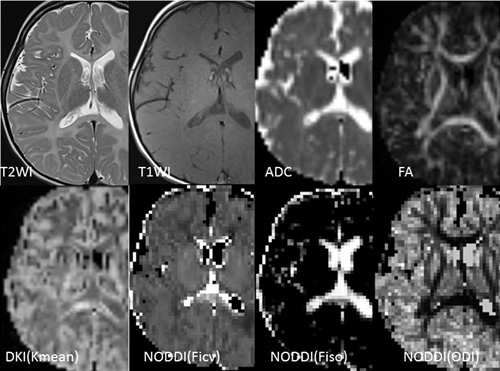

Diffusion images of a case of Pelizaeus-Merzbacher disease (PMD)

PMD is a disorder that shows impaired myelination. T2WI and T1WI indicate loss of the signal from normal white matter. ADC image shows slight increase of the diffusivity in the white matter, and fractional anisotropy (FA) image shows obvious high value along the white matter distribution.

The lower column shows non-Gaussian diffusion images. Diffusion kurtosis image (DKI) shows lower kurtosis except in the splenium. Neurite Orientation Dispersion and Density Imaging (NODDI) shows widespread decrease of the neurite density (Ficv), while free water diffusion (Fiso) and orientation dispersion index (ODI) shows resemble distribution with normal brain.